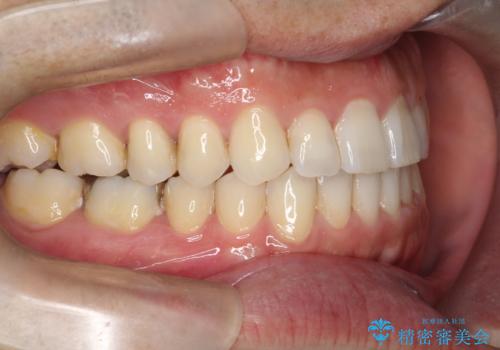

【インビザライン】前歯の隙間を閉じたい

- 前歯の隙間を主訴に来院されました。

マウスピース矯正にて、隙間を綺麗に閉じることができ満足していただきました。

前歯の隙間を閉じる際は、前歯部の突き上げが懸念されるため、適切な治療計画が必要となります。